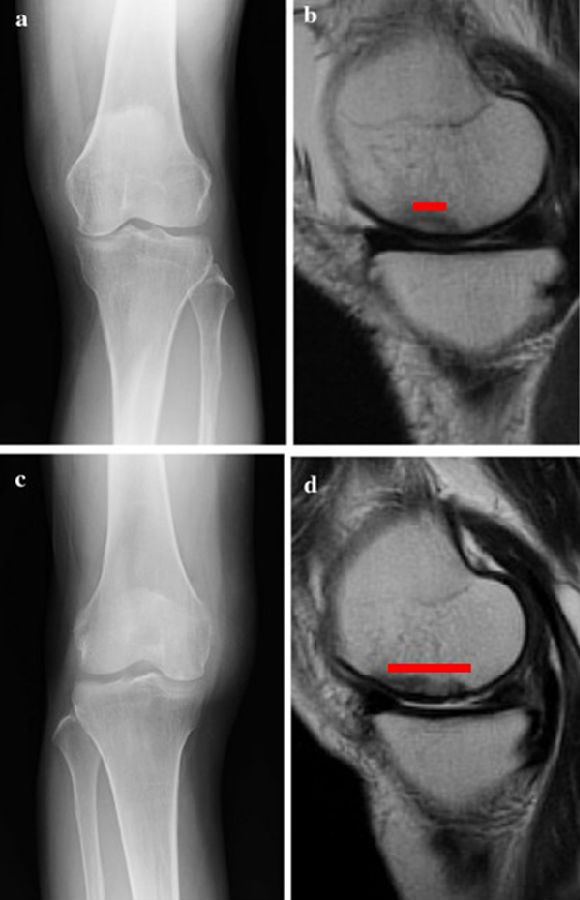

a.患者,59岁女性,AP侧位片显示SONKⅠ期,FTA<180°;b.MRI T2显示病变深度<20mm,患者出现症状1年后保守治疗;c.75岁女性,X线显示SONKⅠ期,FTA>180°;d. MRI T2显示病变深度>20mm,患者于症状出现后11周行手术治疗

影响保守治疗效果的因素